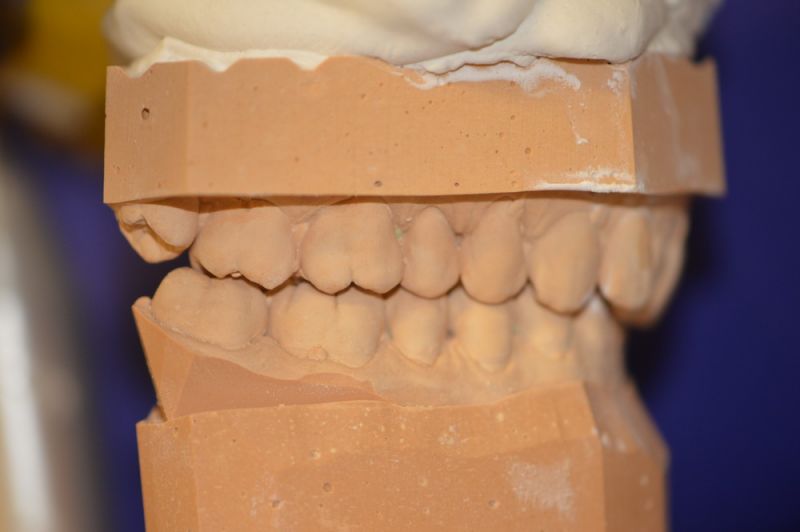

Es läuft dfas Nachweisverfahren einer CMD unter Einsatz eines adjustierten Aufbissbehelfs.

Deutlich erkennbar die Nonokklusion in neuromuskulär zenmtrierter Bisslage